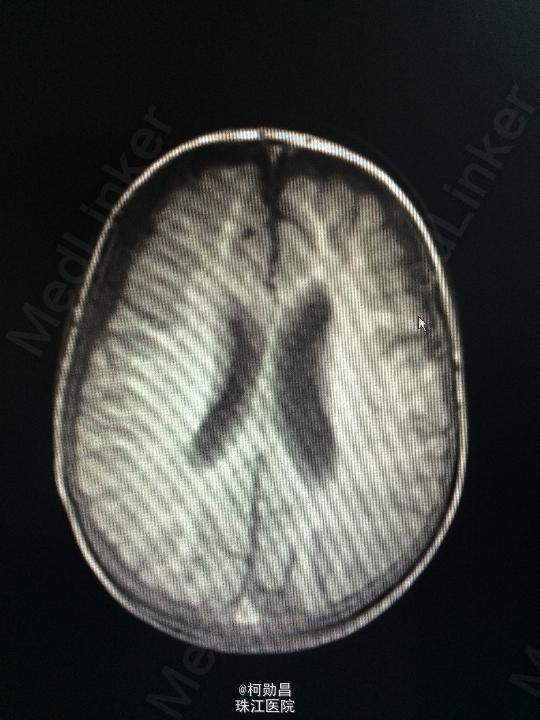

主诉:发热10天,抽搐3天 病史:患儿出生后8个月,因“发热10天,抽搐3天”入院,入院时体温39.3℃,神志不清,反应差。四肢肌张力增高,以双上肢肌力增高明显。病理征未引出。

查体:神志不清,四肢肌力增高 辅助检查:头颅CT提示脑积水并脑脊液外渗,幕上脑室扩张,右侧额颞叶硬膜下脑脊

诊断:化脓性脑膜炎伴脑积水 处理:予内科抗感染治疗,后行脑室腹腔引流术。